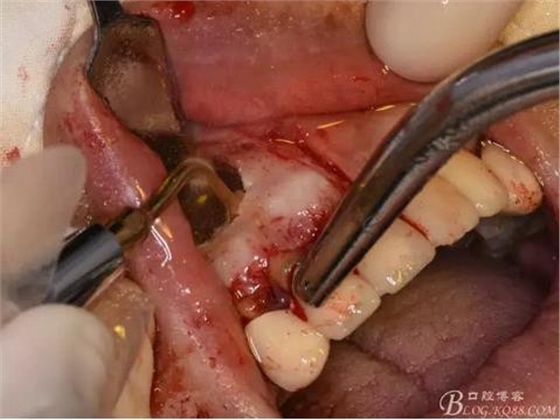

圖7.分別在13的遠(yuǎn)中和11的近中做垂直切口加齦溝內(nèi)水平切口,形成梯形瓣

圖8.翻開梯形瓣

圖9.去除唇側(cè)薄的骨壁,暴露出囊壁